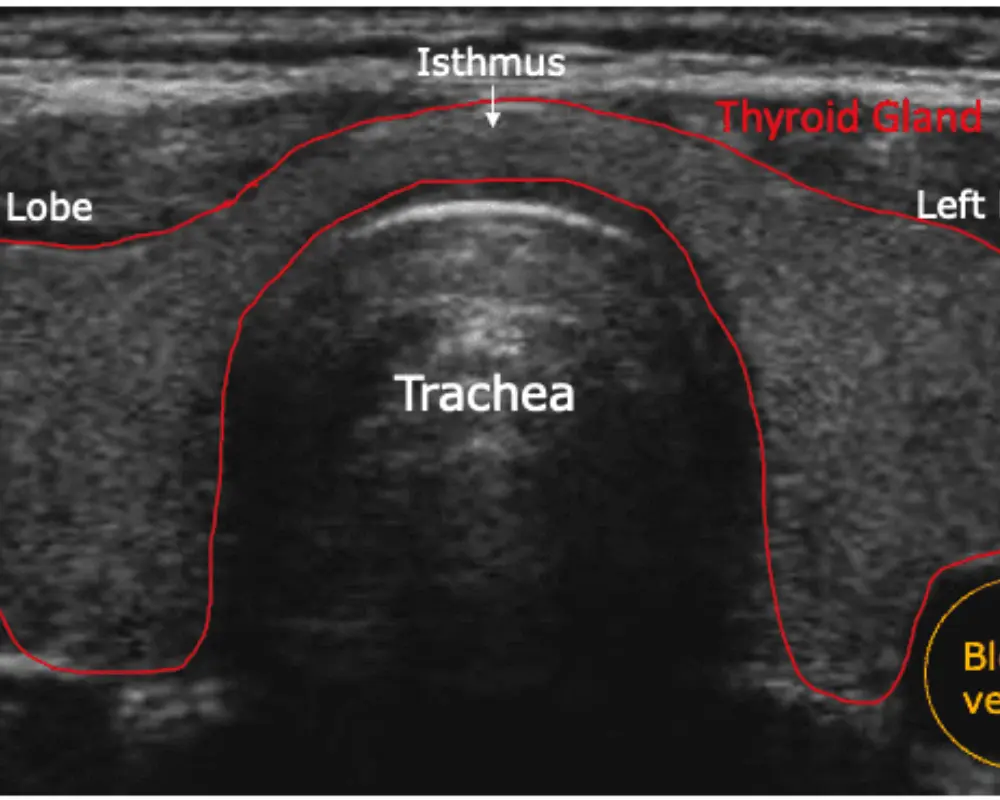

Thyroid Ultrasound

This ultrasound scan examines the thyroid gland to detect nodules, swelling, or abnormalities, helping providers evaluate function and determine the need for further medical care.